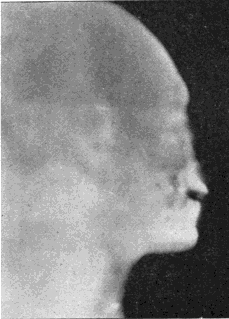

Fig. 1.—Head.